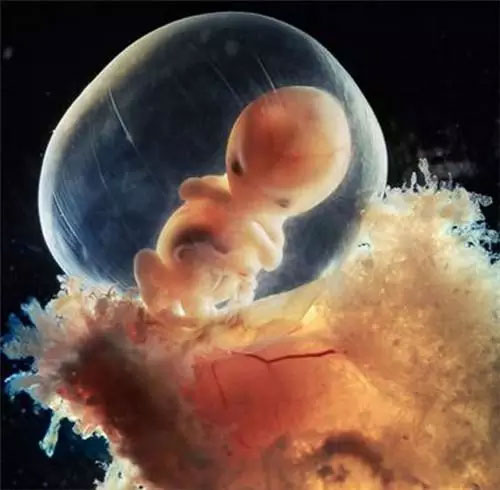

受精后第四周

5周大的胎儿。此时胎儿只有大约9毫米长,面部正在发育,嘴巴、鼻孔和眼睛正在形成

40天,外层胚胎细胞与松散的子宫表层融合,形成胎盘